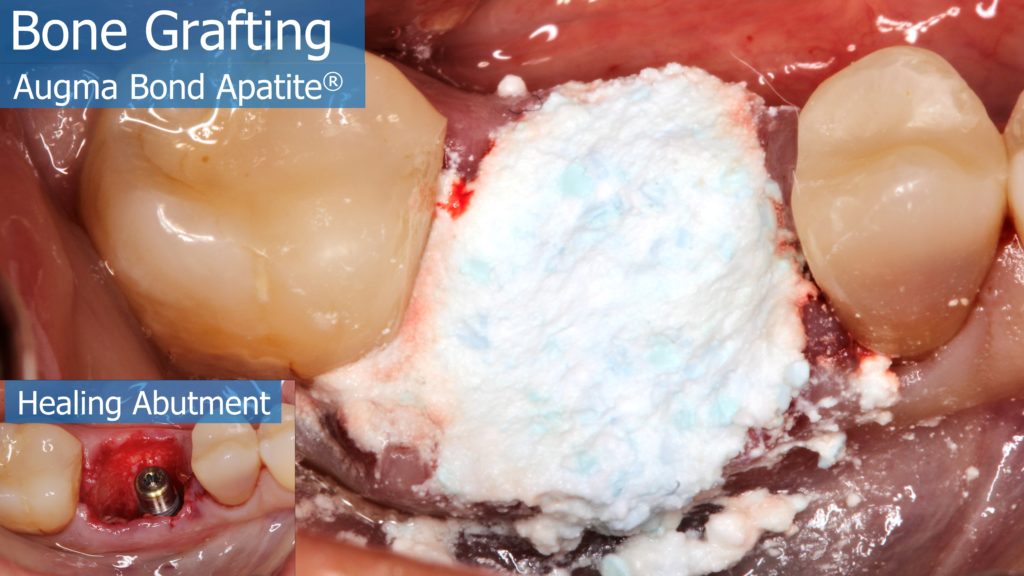

6-12 Months, Augma Bone Cement Academy, Bone Cement Expert, Clinical Cases, Clinical Indication, Clinician, Collagen Sponge/Plug, Coverage Used, Dental Notation, Images, Immediate Placement, Lower Left Molar, Media, Post-Op Period, Socket Grafting, Wound Dressing

A healthy 36 year old woman comes to the clinic with pain and swelling in the area of the inferior left molars. In the intraoral observation, a vestibular fistula was identified, and the complementary exams confirmed a bone lesion caused by a root perforation (poorly executed false post) on the first lower left molar #36 (19). It was decided to do antibiotic therapy for a week and then the tooth extraction with immediate implant placement and bone graft. 4 months post-op the definitive zirconia/ceramic crown would be was made.